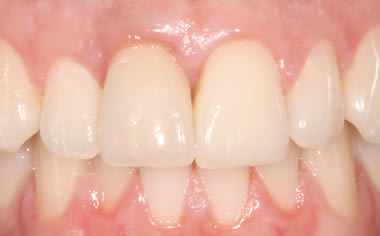

Before & After Gallery

More front teeth replaced by dental implants

Case Three (4 images)